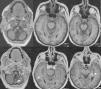

Las malformaciones arteriovenosas (MAV) cerebrales múltiples son poco frecuentes y la mayoría de las publicaciones existentes presentan casos clínicos aislados. Su incidencia en grandes series de MAV oscila entre el 0,3 y 9%, y en la mayoría de casos aparecen asociadas con otras anomalías vasculares del cerebro u otros tejidos. Presentamos el caso clínico de una mujer de 62 años que sufrió una hemorragia parenquimatosa temporal izquierda y que en los estudios neuro-radiológicos se evidenciaron 3 MAV localizadas en: lóbulo temporal izquierdo, hemisferio cerebeloso izquierdo y lóbulo temporal derecho. Las lesiones fueron tratadas con radiocirugía.

Multiple cerebral arteriovenous malformations (AVMs) are thought to be exceedingly rare lesions and have usually been reported as single cases. The incidence of multiple cerebral AVMs in major series ranges from 0.3% to 9% and, in the majority of cases, these malformations are associated with other vascular anomalies of the brain or soft tissues. We report a 62-year-old woman that presented with a left temporal haemorrhage. Angiography showed 3 AVMs located in the left temporal lobe, left cerebellar hemisphere and right temporal lobe. The lesions were treated with radiosurgery.